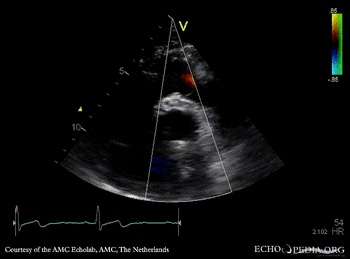

Bentall and aortic valve prosthesis

Courtesy of: AMC Echolab, AMC, The Netherlands

PSAX: aortic valve prosthesis and Bentall in situ PSAX with Color Doppler